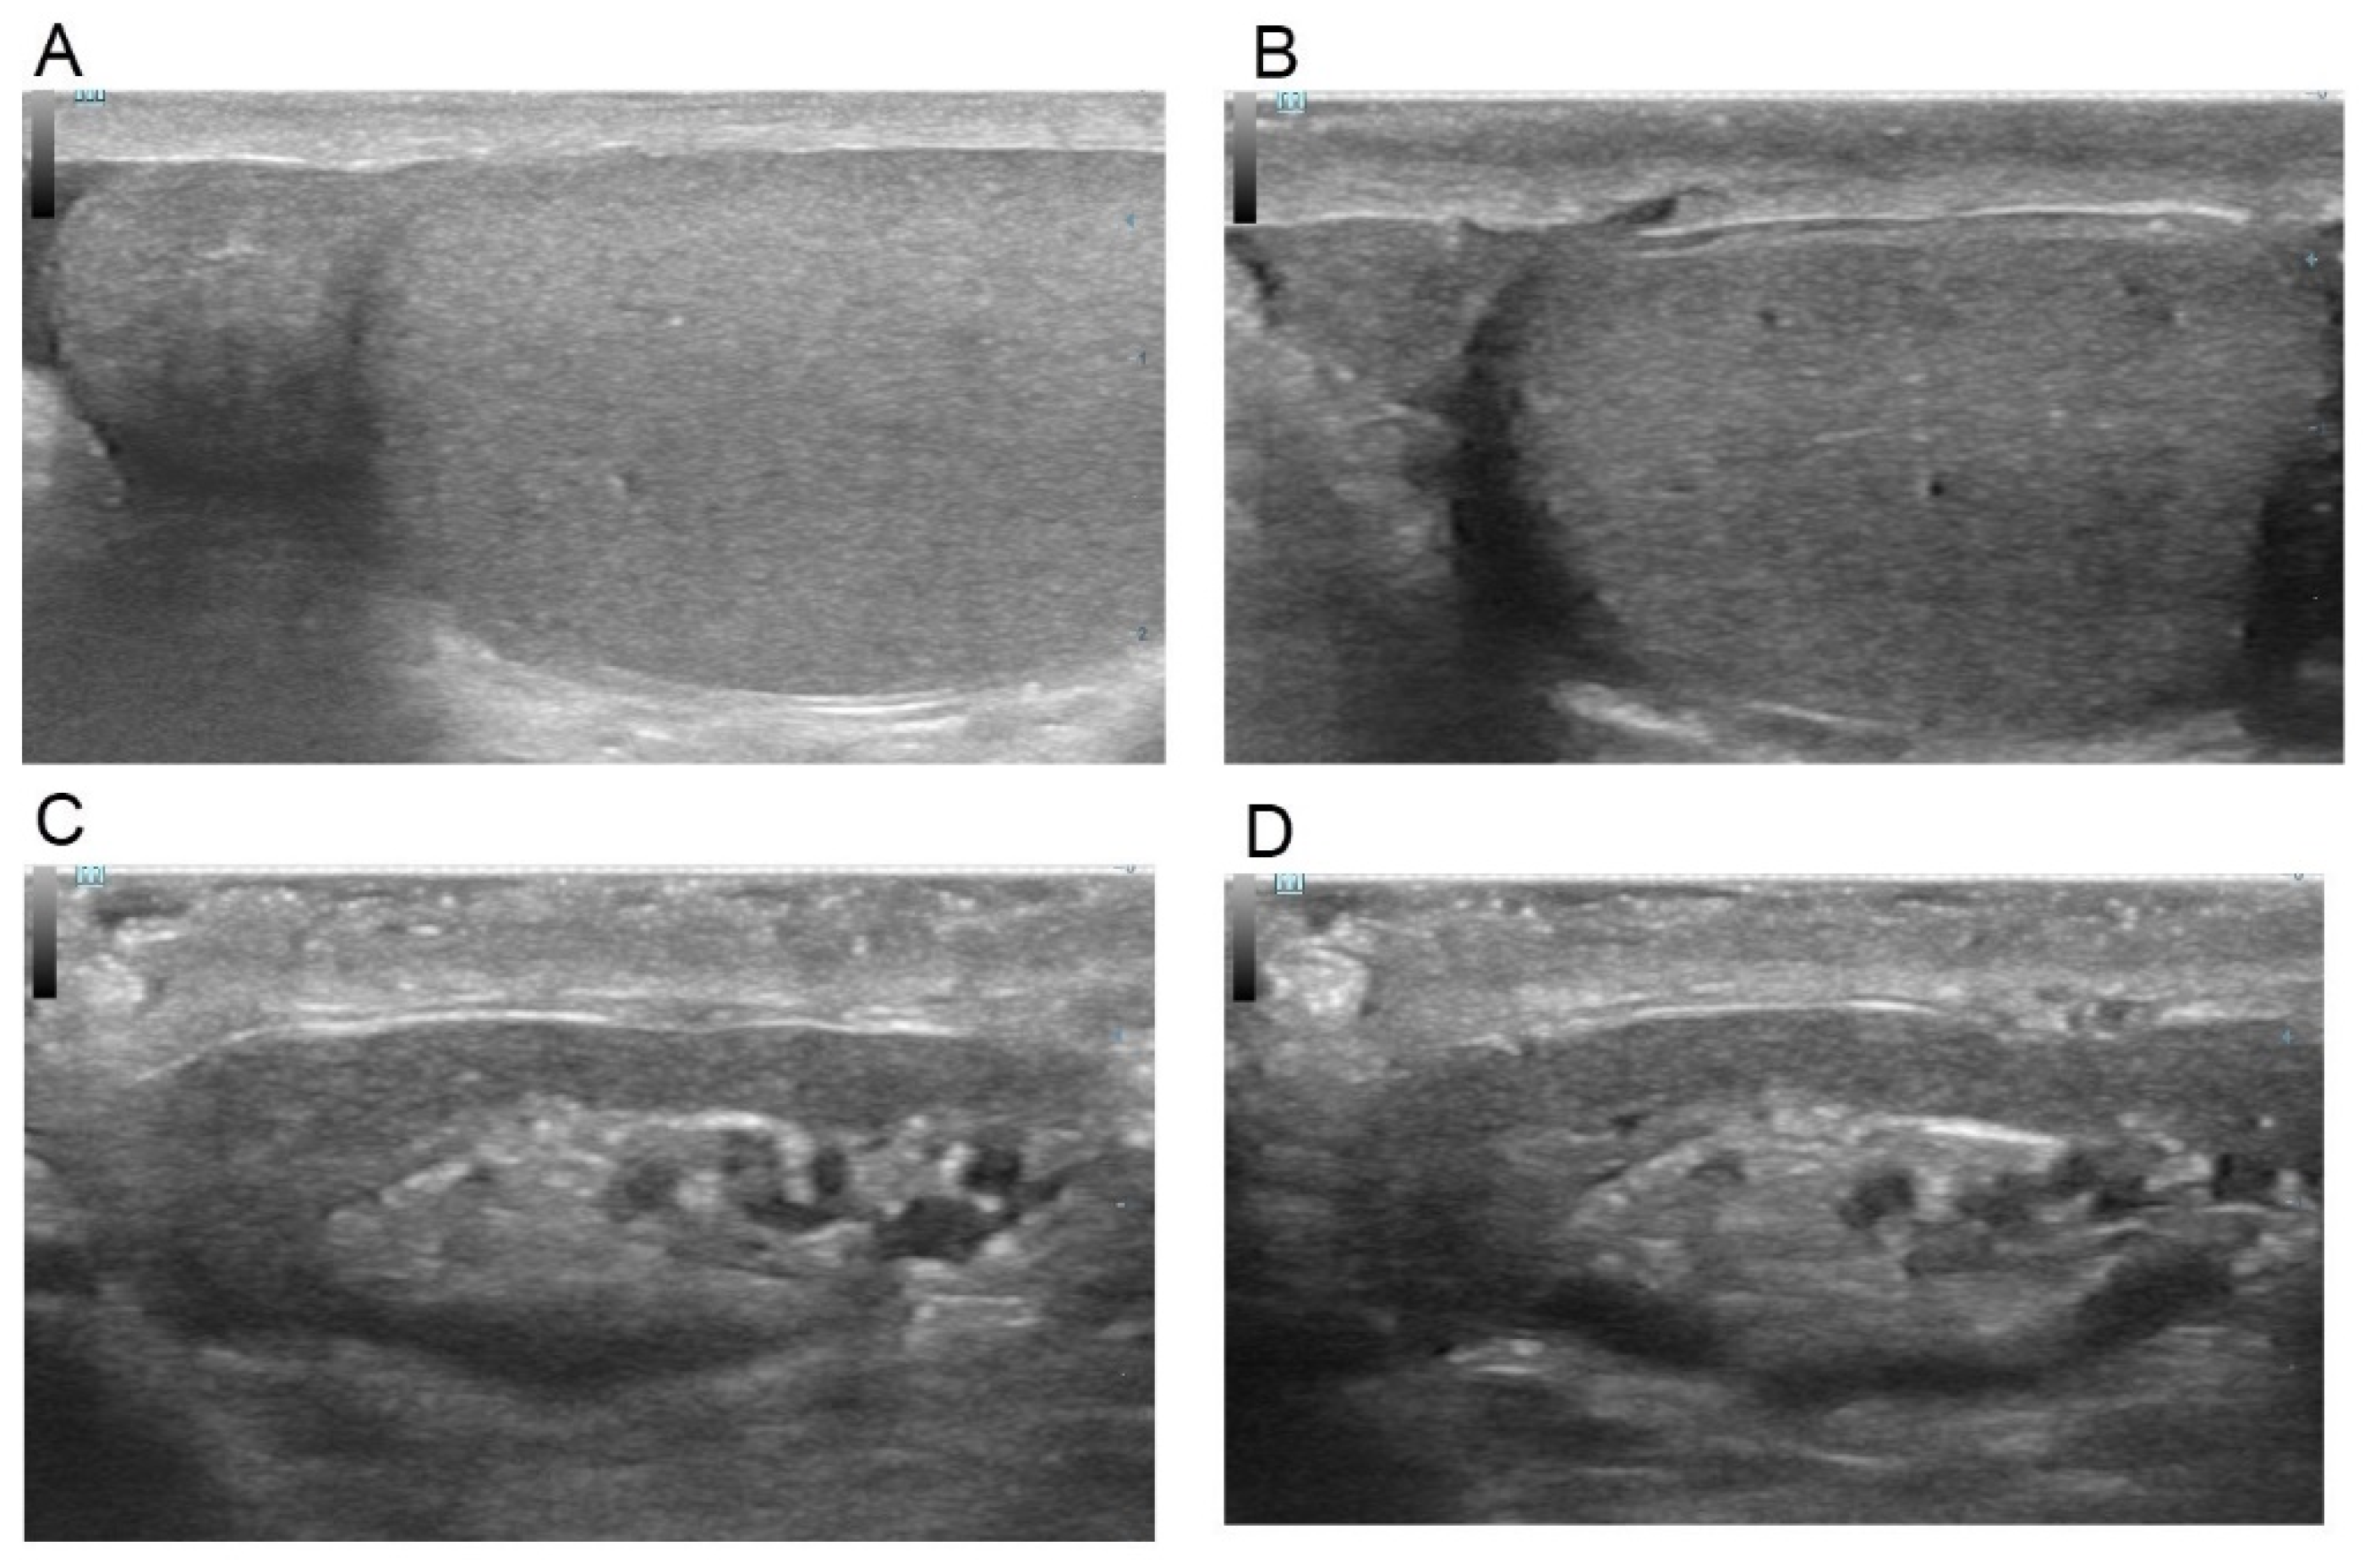

2. Materials and Methods

4. Discussion